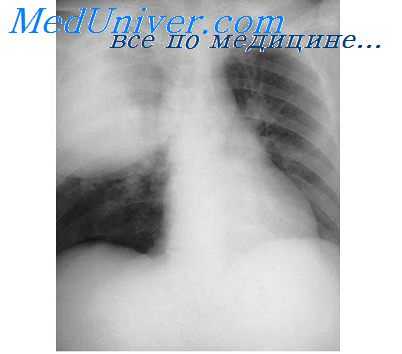

При подозрении на острую пневмонию назначается рентгенография легких в двух проекциях в динамике (на 7-10 день и 3-4 неделе). Рентгенологическим доказательством инфильтративных изменений при крупозной и крупноочаговой пневмонии является сегментарное или долевое гомогенное интенсивное затенение легочной ткани; при бронхопневмонии – неоднородное затенение части доли средней и малой интенсивности с захватом перибронхиальных и периваскулярных участков. В случае замедления рассасывания инфильтратов при острой пневмонии показана КТ легких.

КТ органов грудной клетки. Участок воспалительной инфильтрации (пневмония) в задних каудальных отделах нижней доли правого легкого